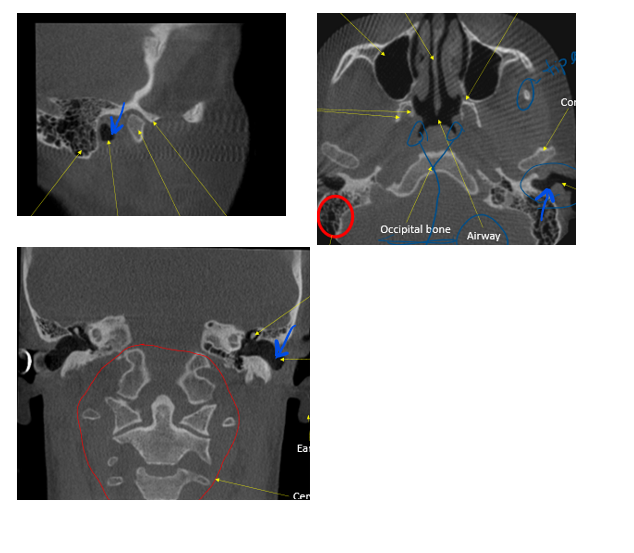

in the circle, indicated by the arrow

place pin on r or l condyle

ID external auditory meatus

bilateral view of TMJ